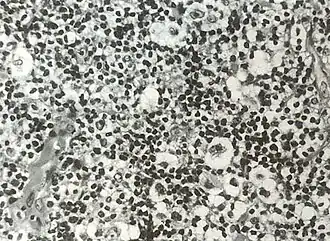

Микропрепарат: биоптат лимфоузла. Характерная клетка Рид — Березовского — Штернберга

Лимфома Ходжкина (синонимы: лимфогранулемато́з[8][9], болезнь Ходжкина, злокачественная гранулёма) — злокачественное заболевание лимфоидной ткани, характерным признаком которого является наличие гигантских клеток Рид — Березовского — Штернберга, обнаруживаемых при микроскопическом исследовании поражённых лимфатических узлов.

Обнаружение гигантских клеток Рид-Березовского-Штернберга и их одноядерных предшественников, клеток Ходжкина, в биоптате есть обязательный критерий диагноза лимфогранулематоза. По мнению многих авторов, только эти клетки являются опухолевыми. Все остальные клетки и фиброз есть отражение иммунной реакции организма на опухолевый рост. Главными клетками лимфогранулематозной ткани, как правило, будут мелкие, зрелые Т-лимфоциты фенотипа CD2, CD3, CD4 > CD8, CD5 с различным количеством В-лимфоцитов. В той или иной степени присутствуют гистиоциты, эозинофилы, нейтрофилы, плазматические клетки и фиброз. Соответственно различают четыре основных гистологических типа: